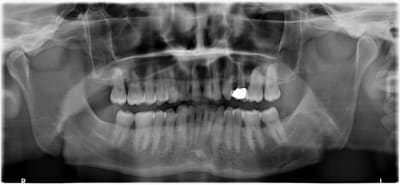

un patient 46 ans de longue date vient me voir pour la casse distale du bridge cantilever maxi gauche, fait sur dent vivante il y a 16 ans, réalisé après de l'ortho, la 14 a été extraite, avec un espace dispo entre 15-13 réduit.

De plus, avec un bilan paro correct,il trouve que les espaces surtout entre 46-47, 16-17 s'agrandissent et lui gênent de plus en plus.

Mais quand meme , on voit sur le haut , des plats d usure de 13 à 22 ET aussi , ce qui est interessant,2petits plats sur les pointes palatines de 17 et 27.

En bas tu t en doutes le pb vient de 33 , bien sur .

Sa 33 (export comme dirait CariGrant ) qui a probablement tendance a devenir de plus en plus oblique avec le racourcissement de l arc , pousse la mand vers la droite .

La démarche est son bridge.

Le bourrage annexe mais l évolution me questionne.

L ortho a été fait tardivement vers 20 ans pour des raisons esthêtiques. La 24 extraite mais semble t il , l ortho n a pas pu fermé l espace.

Mastication surtout droite pour êviter d abimer son bridge depuis des lustres.

Son guidage droit est plus simple , que le gauche.

Ouille je n’avais pas pensé à ça ... et pour la gestion des espaces au niveau molaire ? Je suppose que les dents sont saines

Changer le bridge ne me gêne pas .

C'est surtout , comprendre le mécanisme de distalisation des 7, car ça va se terminer par du bourrage qui va s'accroître, donc poche donc extraction plus tard..

Oui déjà maintenant ça a pas l’air terrible en mésial de la 17...ça donne quoi les sondages ?